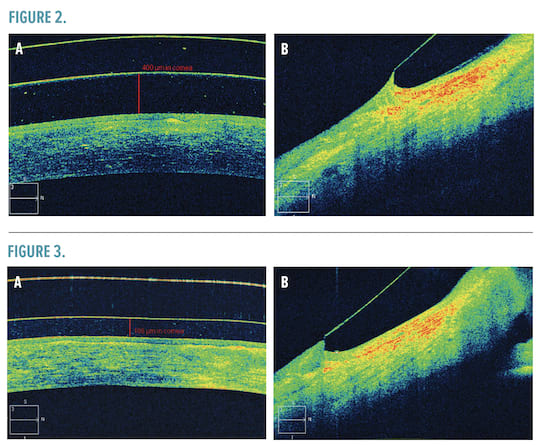

After placing an initial trial lens—SynergEyes VS (CooperVision Specialty EyeCare—SynergEyes)-—on the right eye, an OCT image was obtained, showing excessive central clearance as well as a slightly tight fitting relationship 360 degrees (Figure 2a-b). As the initial lens has a sagittal depth of 3600 microns and peripheral curves of 36/42, it was determined that the initial lens ordered would be 3400 microns in depth and have peripheral curve values of 34/40. An over-refraction over the trial lens revealed a final endpoint of +1.75 -1.50 x 170. Evaluation of the trial lens revealed the flat axis had rotated to 130 degrees.

Another OCT image was obtained upon dispensing of the lens (Figure 3a-b). Central clearance after 20 minutes of settling revealed a clearance of 188 microns. The relationship of the peripheral curves to the globe were much improved. Visual acuity of the right eye was 20/20 with no over-refraction. Upon completion of training with staff regarding proper insertion, removal, and lens care, the patient was released for follow-up care. Several years later, the patient continues to report improvement in subjective symptoms and overall vision.